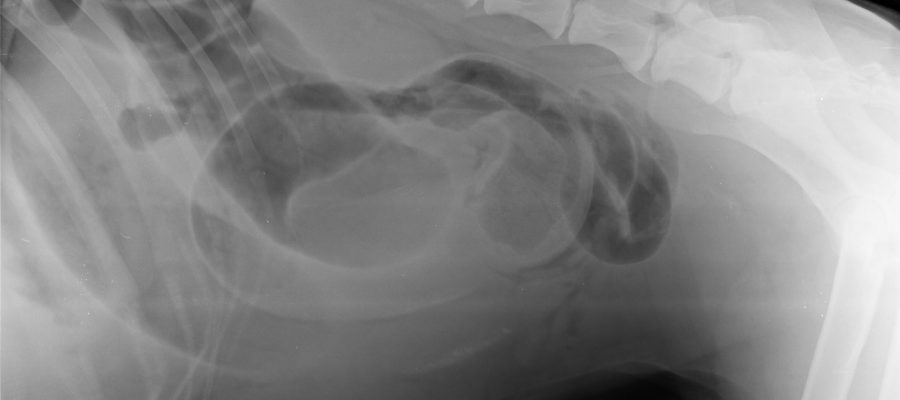

Ovdje objavljujem prvu rtg sliku, ali ne znam da li je to slika rendgena od 13. ili 14. travnja 2021. i da li je to zaista rendgen moga psa jer nema nigdje moga imena ili imena moga psa. Nakon toliko dana, taj nalaz može biti podmetnut i ne mora biti slika moga psa.